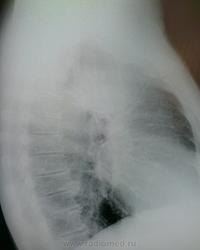

Триада: пневмония в S 2 справа. инфильтративный Твс( более вероятно-ИМХО), С-r.

Описала, как пневмонию под вопросом. Мучаюсь теперь...

Скорее всего не "она". Что посоветуете, ждать контроль после а/б-терапии или вызывать?

Мало надежды на пневмонию,рак будет.Для успокоения совести дождаться контроля и к онкологам.Это не туберкулёз,там при таких размерах должен быть распад с отсевом.

Не очень то тянет на рак,больше на инфильтративный процесс.Специфический или не специфика ,покажет динамика.

Похоже на плеврит осумкованный.